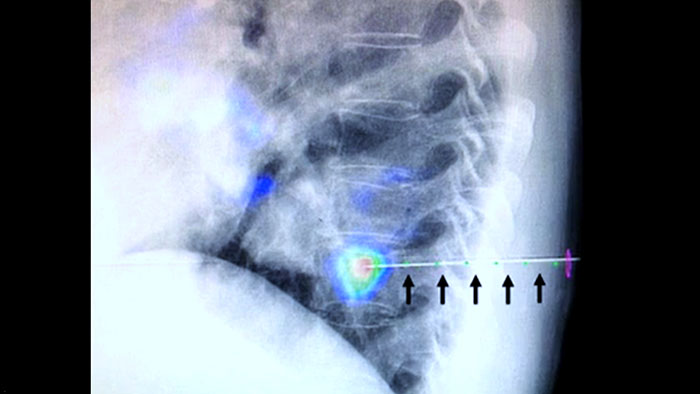

Guía de la trayectoria en vivo con XperGuide

XperGuide proporciona una guía de imagen en vivo de alta precisión de cada aguja a una posición determinada mediante la superposición de trayectorias preplanificadas con imágenes fluoroscópicas.3